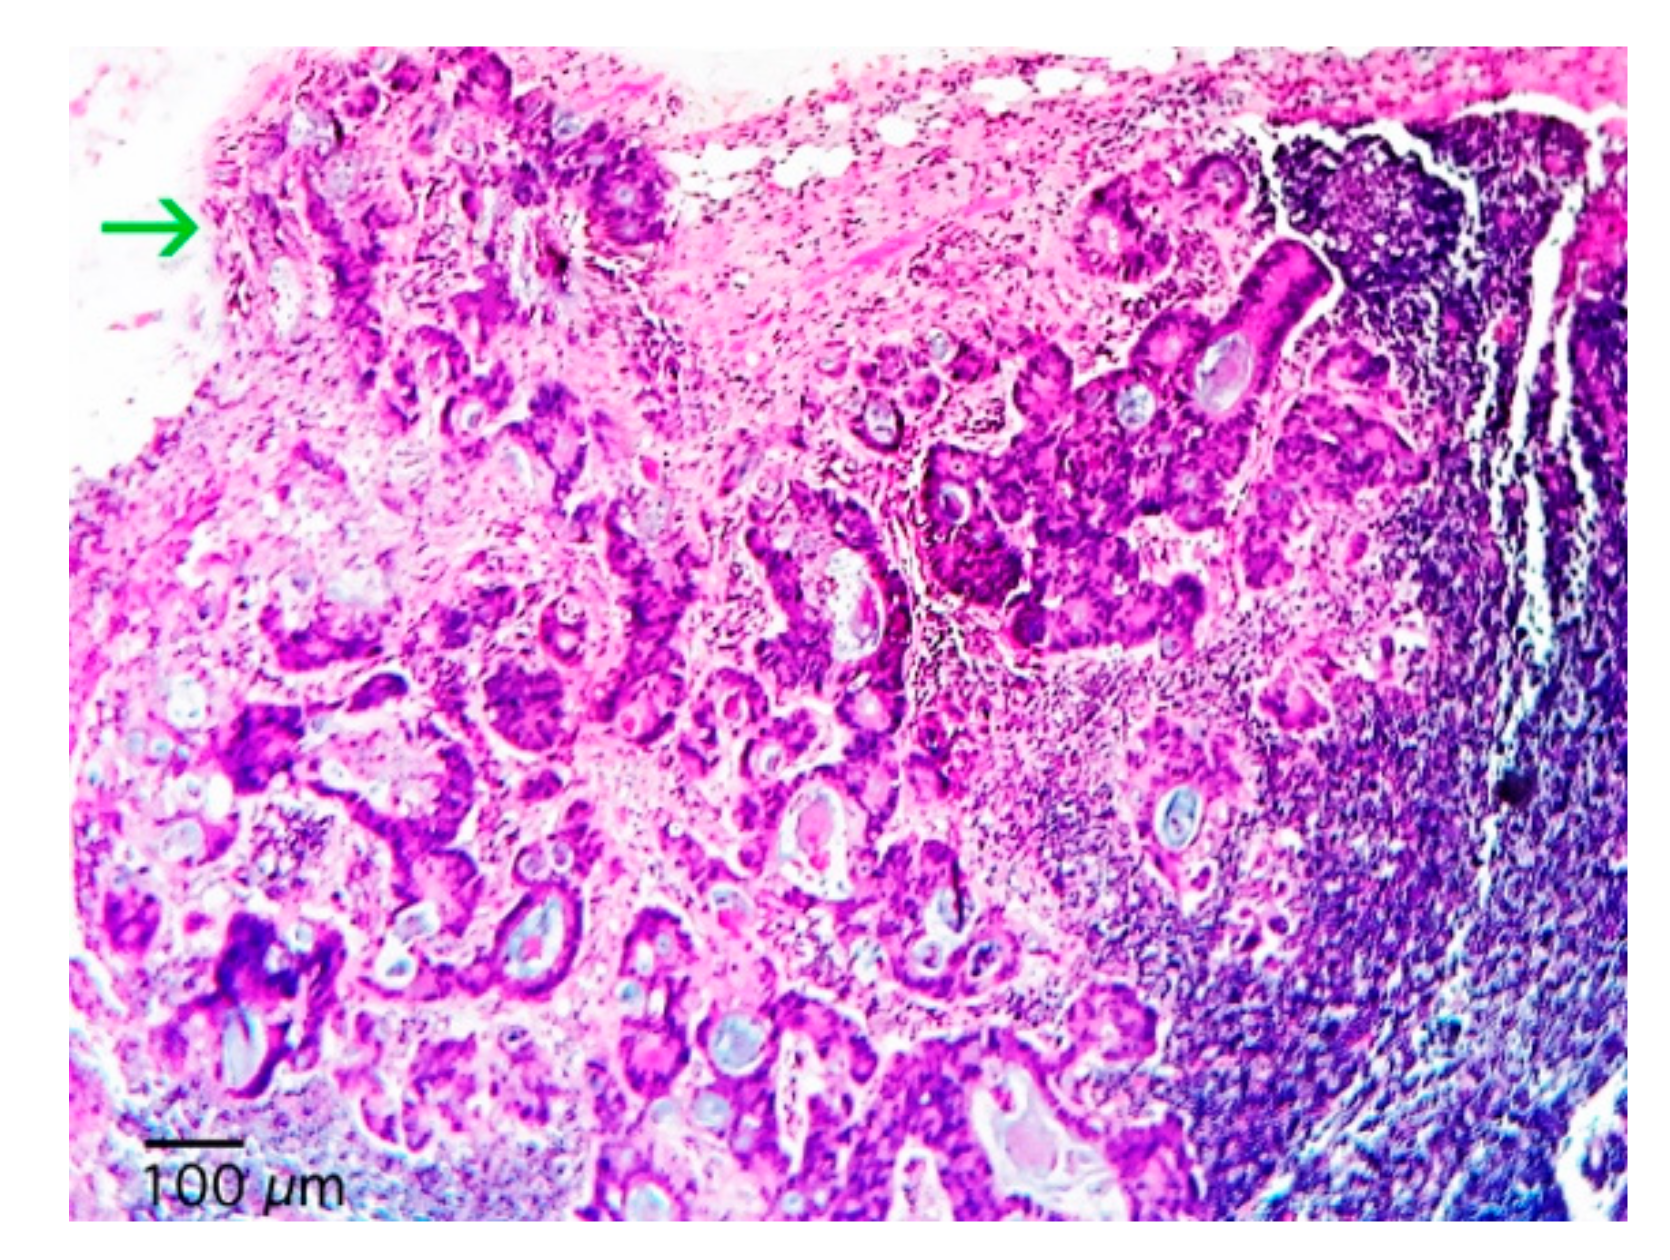

| Extracapsular Extension - No (%) | |

| No | 82 (65.1) |

| Yes | 44 (34.9) |